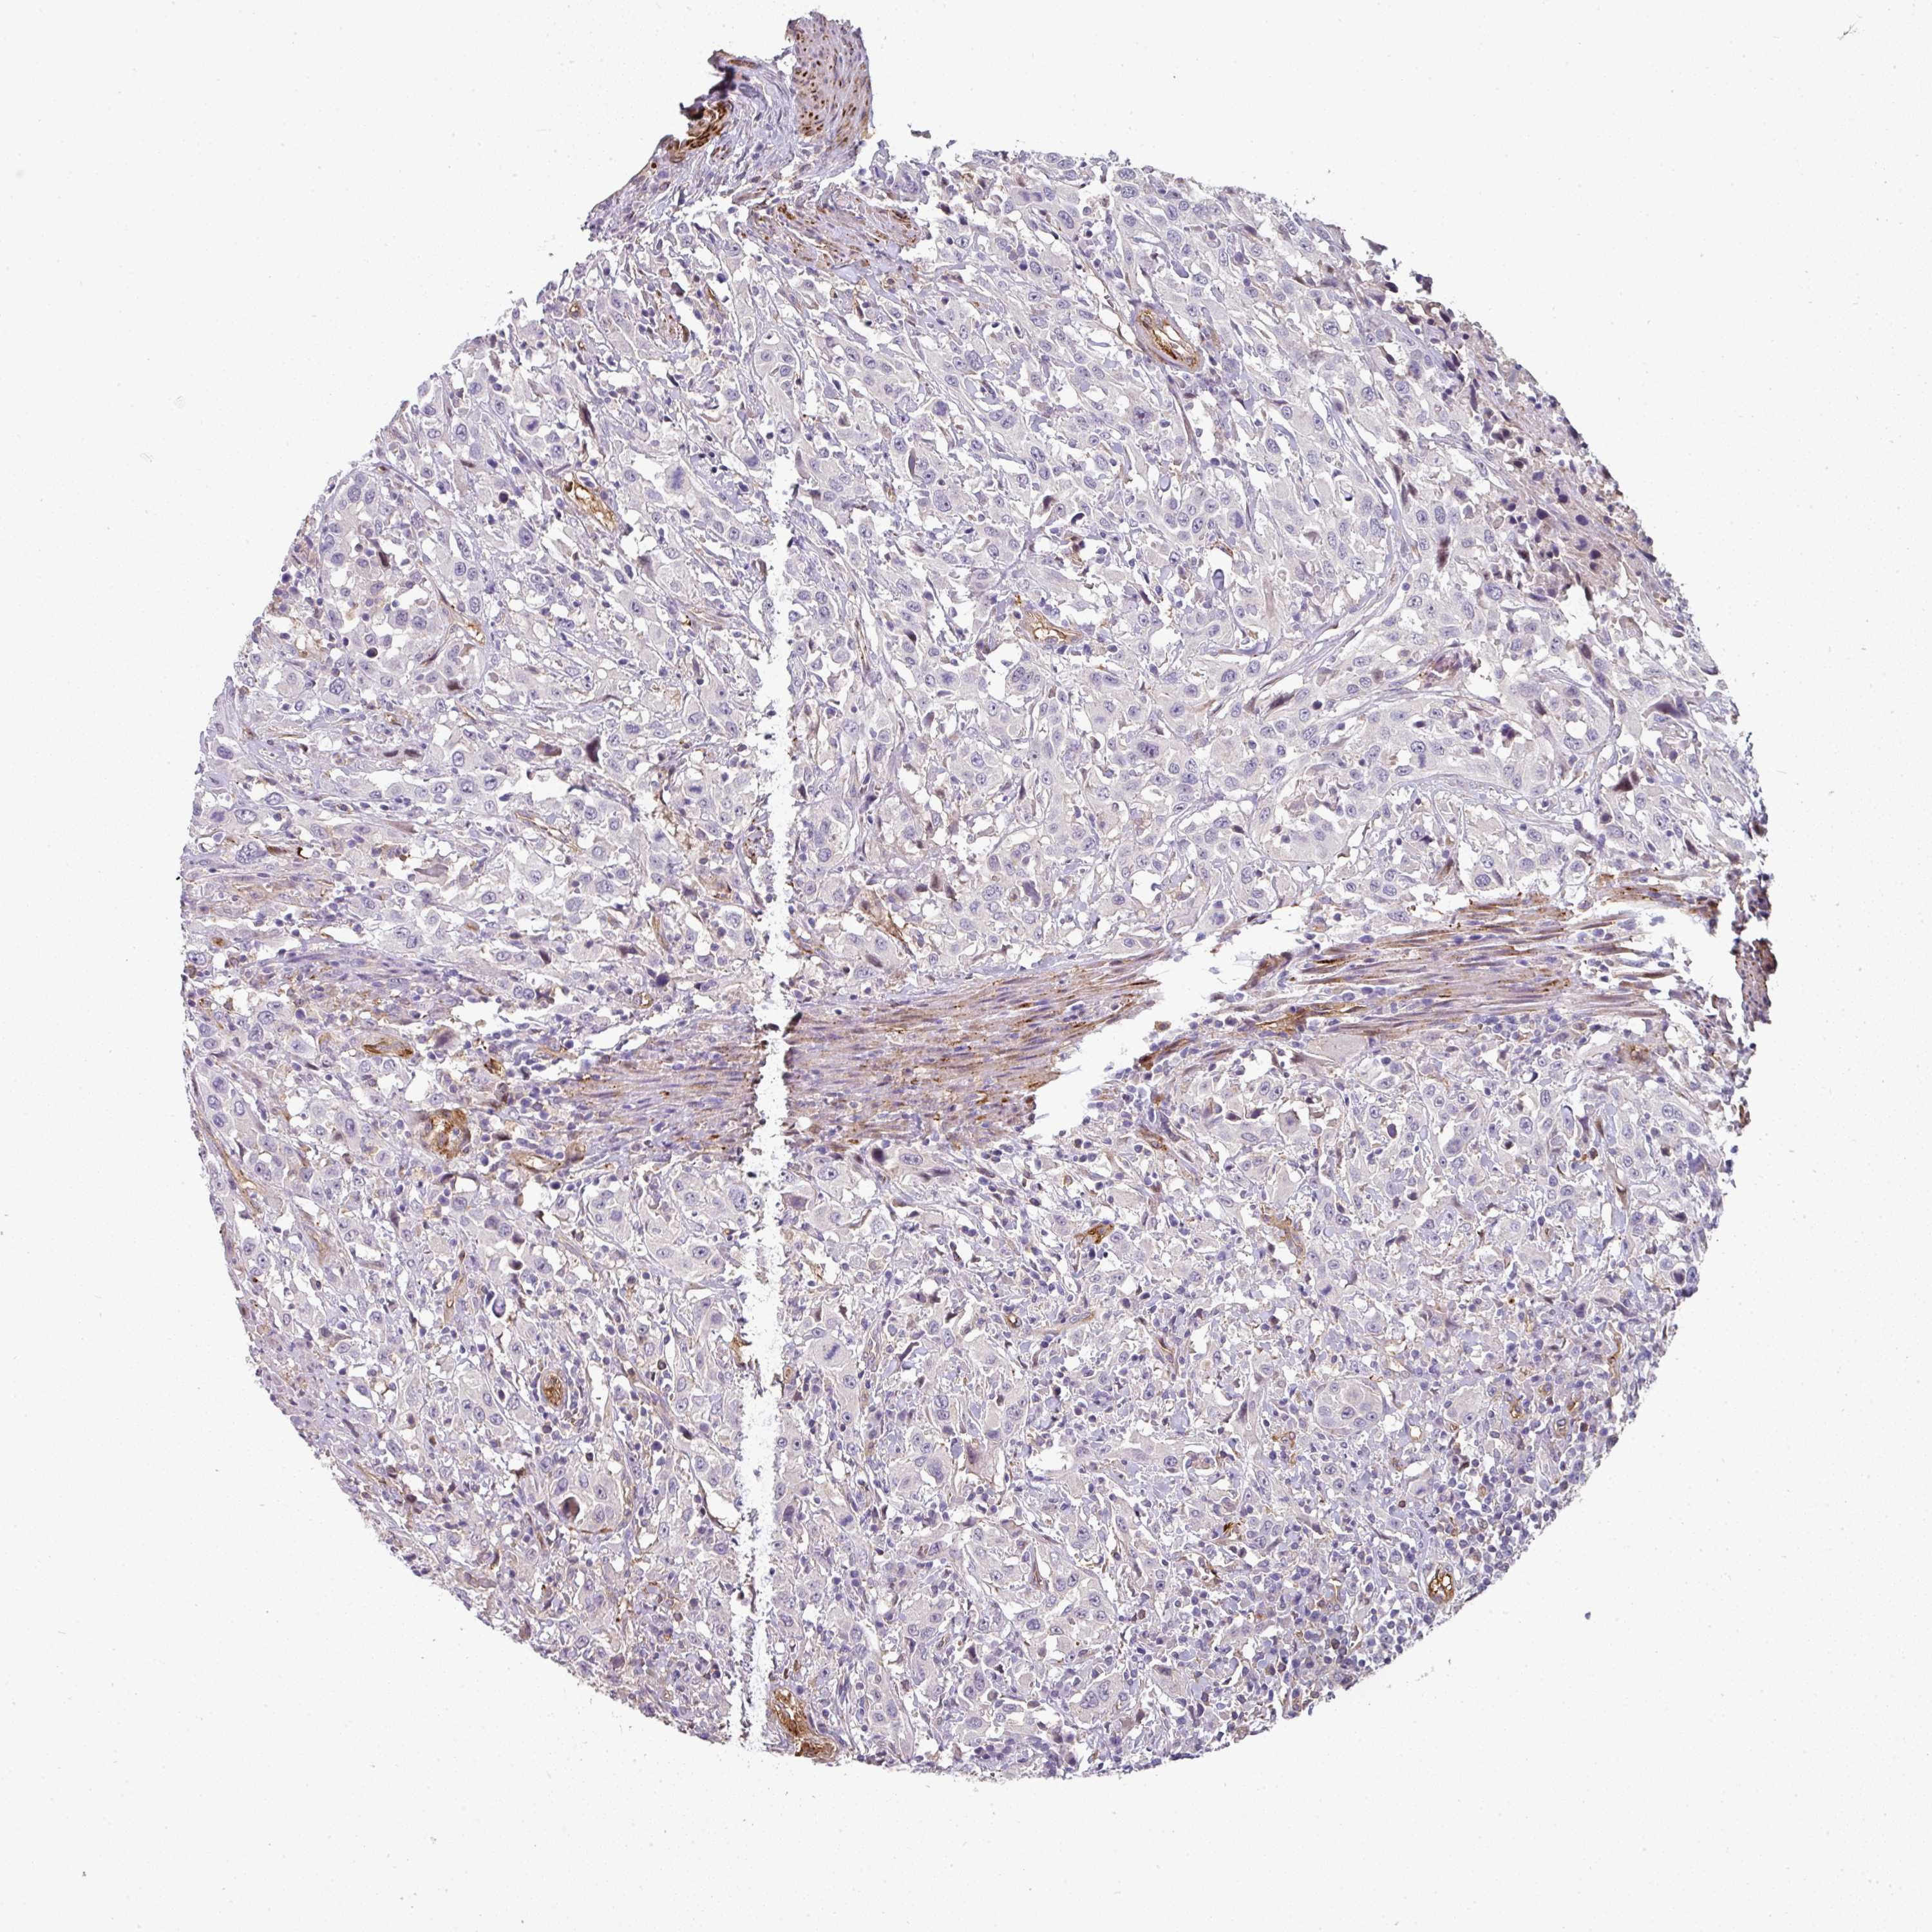

UROTHELIAL CANCER - Protein expressioni

A mouse-over function shows sample information and annotation data. Click on an image to view it in a full screen mode. Samples can be filtered based on level of antibody staining by selecting one or several of the following categories: high, medium, low and not detected. The assay and annotation is described here.

Antibody stainingi

Antibody staining in the annotated cell types in the current human tissue is reported as not detected, low, medium, or high, based on conventional immunohistochemistry profiling in selected tissues. This score is based on the combination of the staining intensity and fraction of stained cells.

Each image is clickable and will lead to virtual microscopy that enables deeper exploration of all samples and also displays staining intensity scores, fraction scores and subcellular localization as well as patient and tissue information for each sample.

Antibody HPA054347

Antibody HPA058007

Urothelial carcinoma, High grade

Urothelial carcinoma, NOS

Urothelial carcinoma, Low grade